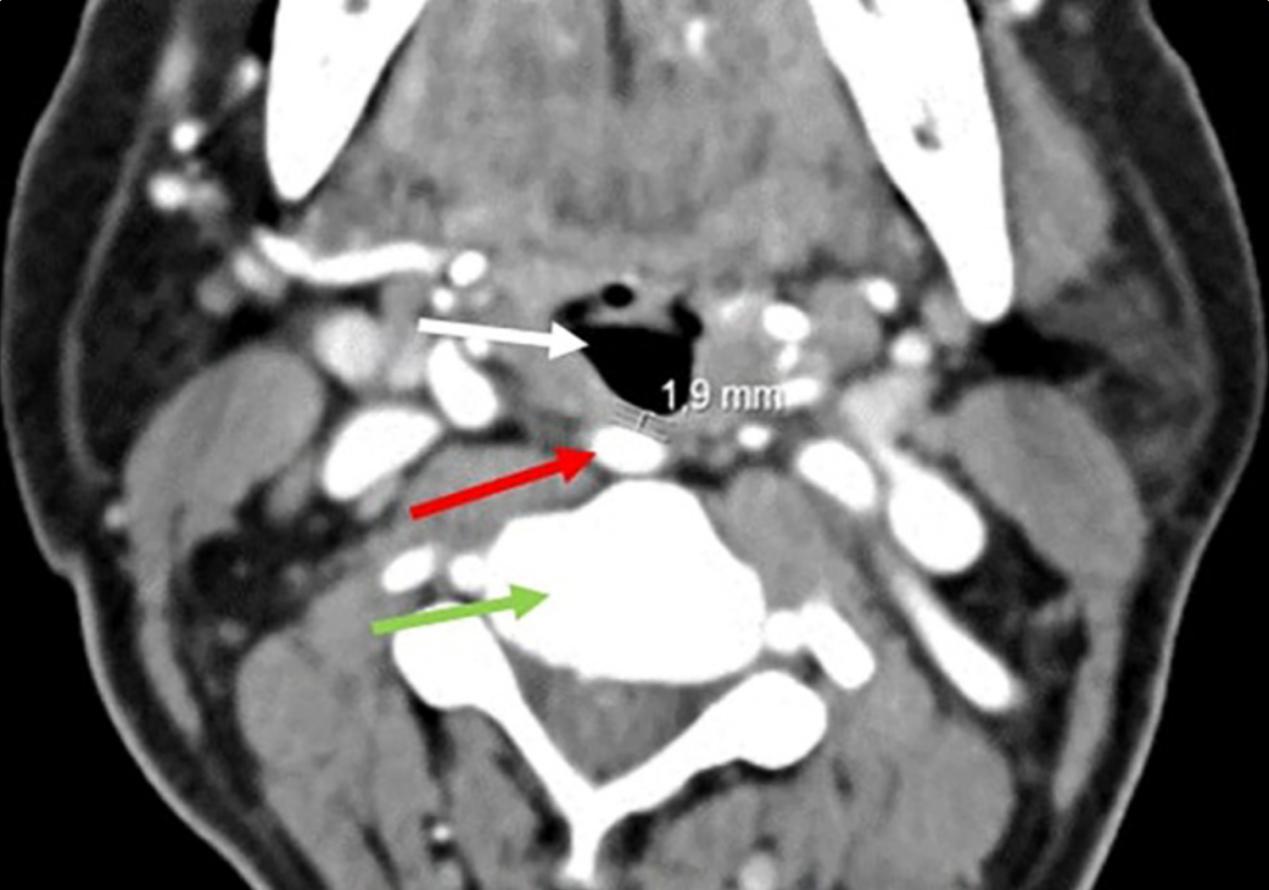

1965年,Weibel和Fields提出了一个分类系统来研究颈动脉异常在脑血管功能不全中的作用。他们根据与垂直平面的偏差区分了三种类型的走形。这种分类的主要局限是缺乏与咽壁距离的概念,这在临床和手术中具有重要意义。因此,Pfeiffer和Ridder在2008年提出了修改,增加了与咽壁的最小距离、异常位置以及由此产生的ICA损伤风险等数据。根据这一分类,我们的患者应为III级,因为其下咽位置 距离咽后壁最小距离为1.9mm(图5),在进行手术时有很高的损伤风险。

图5 在C3水平(绿色箭头)颈内动脉(红色箭头)和咽后壁之间的最小距离为1.9 mm。下咽间隙(白色箭头)被颈动脉凸起压迫